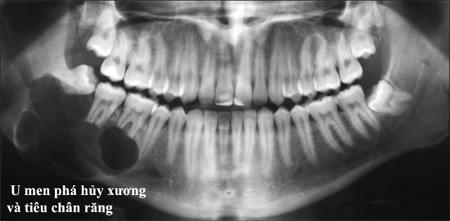

- Trước hết, chúng ta nên biết rằng, đa số các khối u xương hàm, nhất là các khối u lành tính đều không có biểu hiện lâm sàng. Hầu như không có dấu hiệu nào báo trước là có khối u đang phá hủy xương hàm. Thông thường bệnh nhân U xương hàm đến khám và điều trị khi xương đã bị phá hủy và gây biến dạng một phần khuôn mặt. Một vài dấu hiệu nghèo nàn như các răng xô lệch, hoặc lung lay có thể là dấu hiệu lâm sàng đầu tiên của bệnh, nhưng lúc này thường là bệnh đã tiến triển rất nặng rồi.

Cũng có những trường hợp u ác tính xương hàm, dấu hiệu lâm sàng không hề biểu hiện ra ngoài mà chỉ có đơn thuần là dấu hiệu đau nhức răng. Bệnh nhân mất nhiều thời gian chữa tủy răng, rồi sau cùng nhổ răng, vẫn không giải quyết được tình trạng đau ban đầu, cho đến khi đến bệnh viện chụp phim, tình cờ phát hiện khối u xương hàm và đã là u ác tính

- Cách duy nhất là chụp phim khảo sát xương hàm định kỳ mỗi năm. Trước đây máy chụp phim toàn cảnh chỉ có một số cơ sớ lớn chuyên ngành răng hàm mặt trang bị như bệnh viện răng hàm mặt trung ương, bệnh viện răng hàm mặt thành phố và Khoa răng hàm mặt đai học y dược thành phố Hồ Chí Minh. Hiện nay, có một số cơ sở nha khoa tư nhân đã trang bị máy chụp phim toàn cảnh loại bình thường và cả loại kỹ thuật số cho hình ảnh chất lượng. Cần lưu ý là những cơ sở chụp phim X quang tổng quát y khoa không có trang bị loại máy này. Với những máy chụp phim y khoa thông thường, để đánh giá các cấu trúc xương hàm mặt cần phải chụp nhiều phim mới có thể khảo sát tất cả các cấu trúc xương. Phim toàn cảnh không chỉ cho phép khảo sát và tầm soát khối u xương hàm mà còn cho phép đánh giá bệnh lý nha chu, bệnh lý sâu răng. Ngoài phim toàn cảnh, phim cắt lớp điện toán (CT Scan) cũng có thể giúp phát hiện bệnh lý xương hàm, tuy nhiên do lượng tia rất cao của máy, nên phim này chỉ được bác sĩ chỉ định chụp bổ sung khi đã xác định có bệnh lý xương hàm trên phim toàn cảnh và cần chụp thêm CT để đánh giá chi tiết hơn.